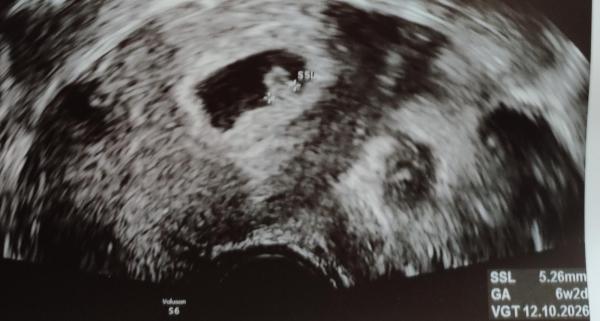

Hallo kinderwunsch88!  Ich setze mich nun ganz offiziell auch dazu! Ich hatte heute meinen ersten Ultraschall laut meiner Berechnung wäre ich nun 6+4 die Ärztin hat aber 6 + 2 datiert.. ich bin so aufgeregt und freue mich riesig! Das Herzchen hat auch schon kräftig geschlagen 😍 Termin im Eltern Kind Pass auf 10.10. datiert 🐥🥳. Wie geht's dir? Und wer setzt sich noch zu uns? Ganz liebe Grüße aus Wien .. Ayaka+ Mäuschen (6+2)

Bild zu